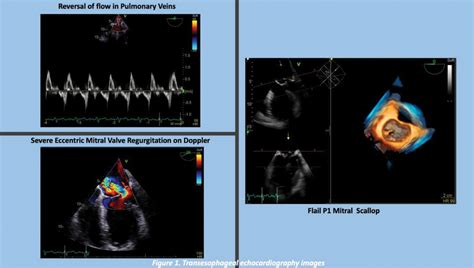

Diagnostic imaging and testing are crucial for confirming the presence and severity of the shunt. Clinicians typically utilize the following tools:

Echocardiography Visualizes blood flow and identifies structural septal defects.

Bubble Study Uses agitated saline to track the movement of bubbles across heart chambers.

⚠️ Note: A bubble study is particularly effective at identifying a PFO or atrial septal defect, as the microbubbles act as a contrast agent that can be easily visualized crossing the septum on an echocardiogram.